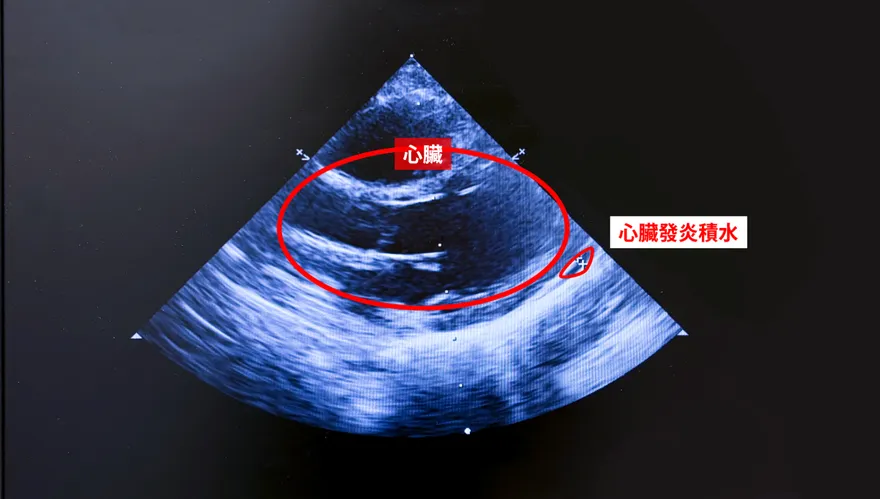

1歲童反覆高燒眼紅嘴腫 確診川崎氏症險釀心臟併發症

心臟超音波